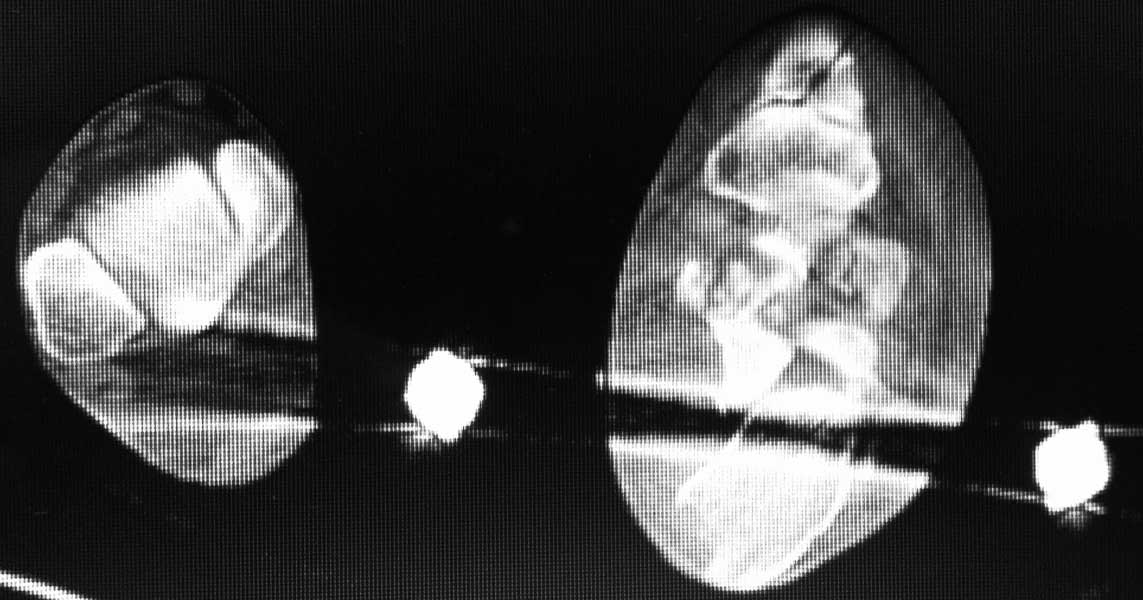

Re: Перелом пяточной кости - ваше мнение?

КТ